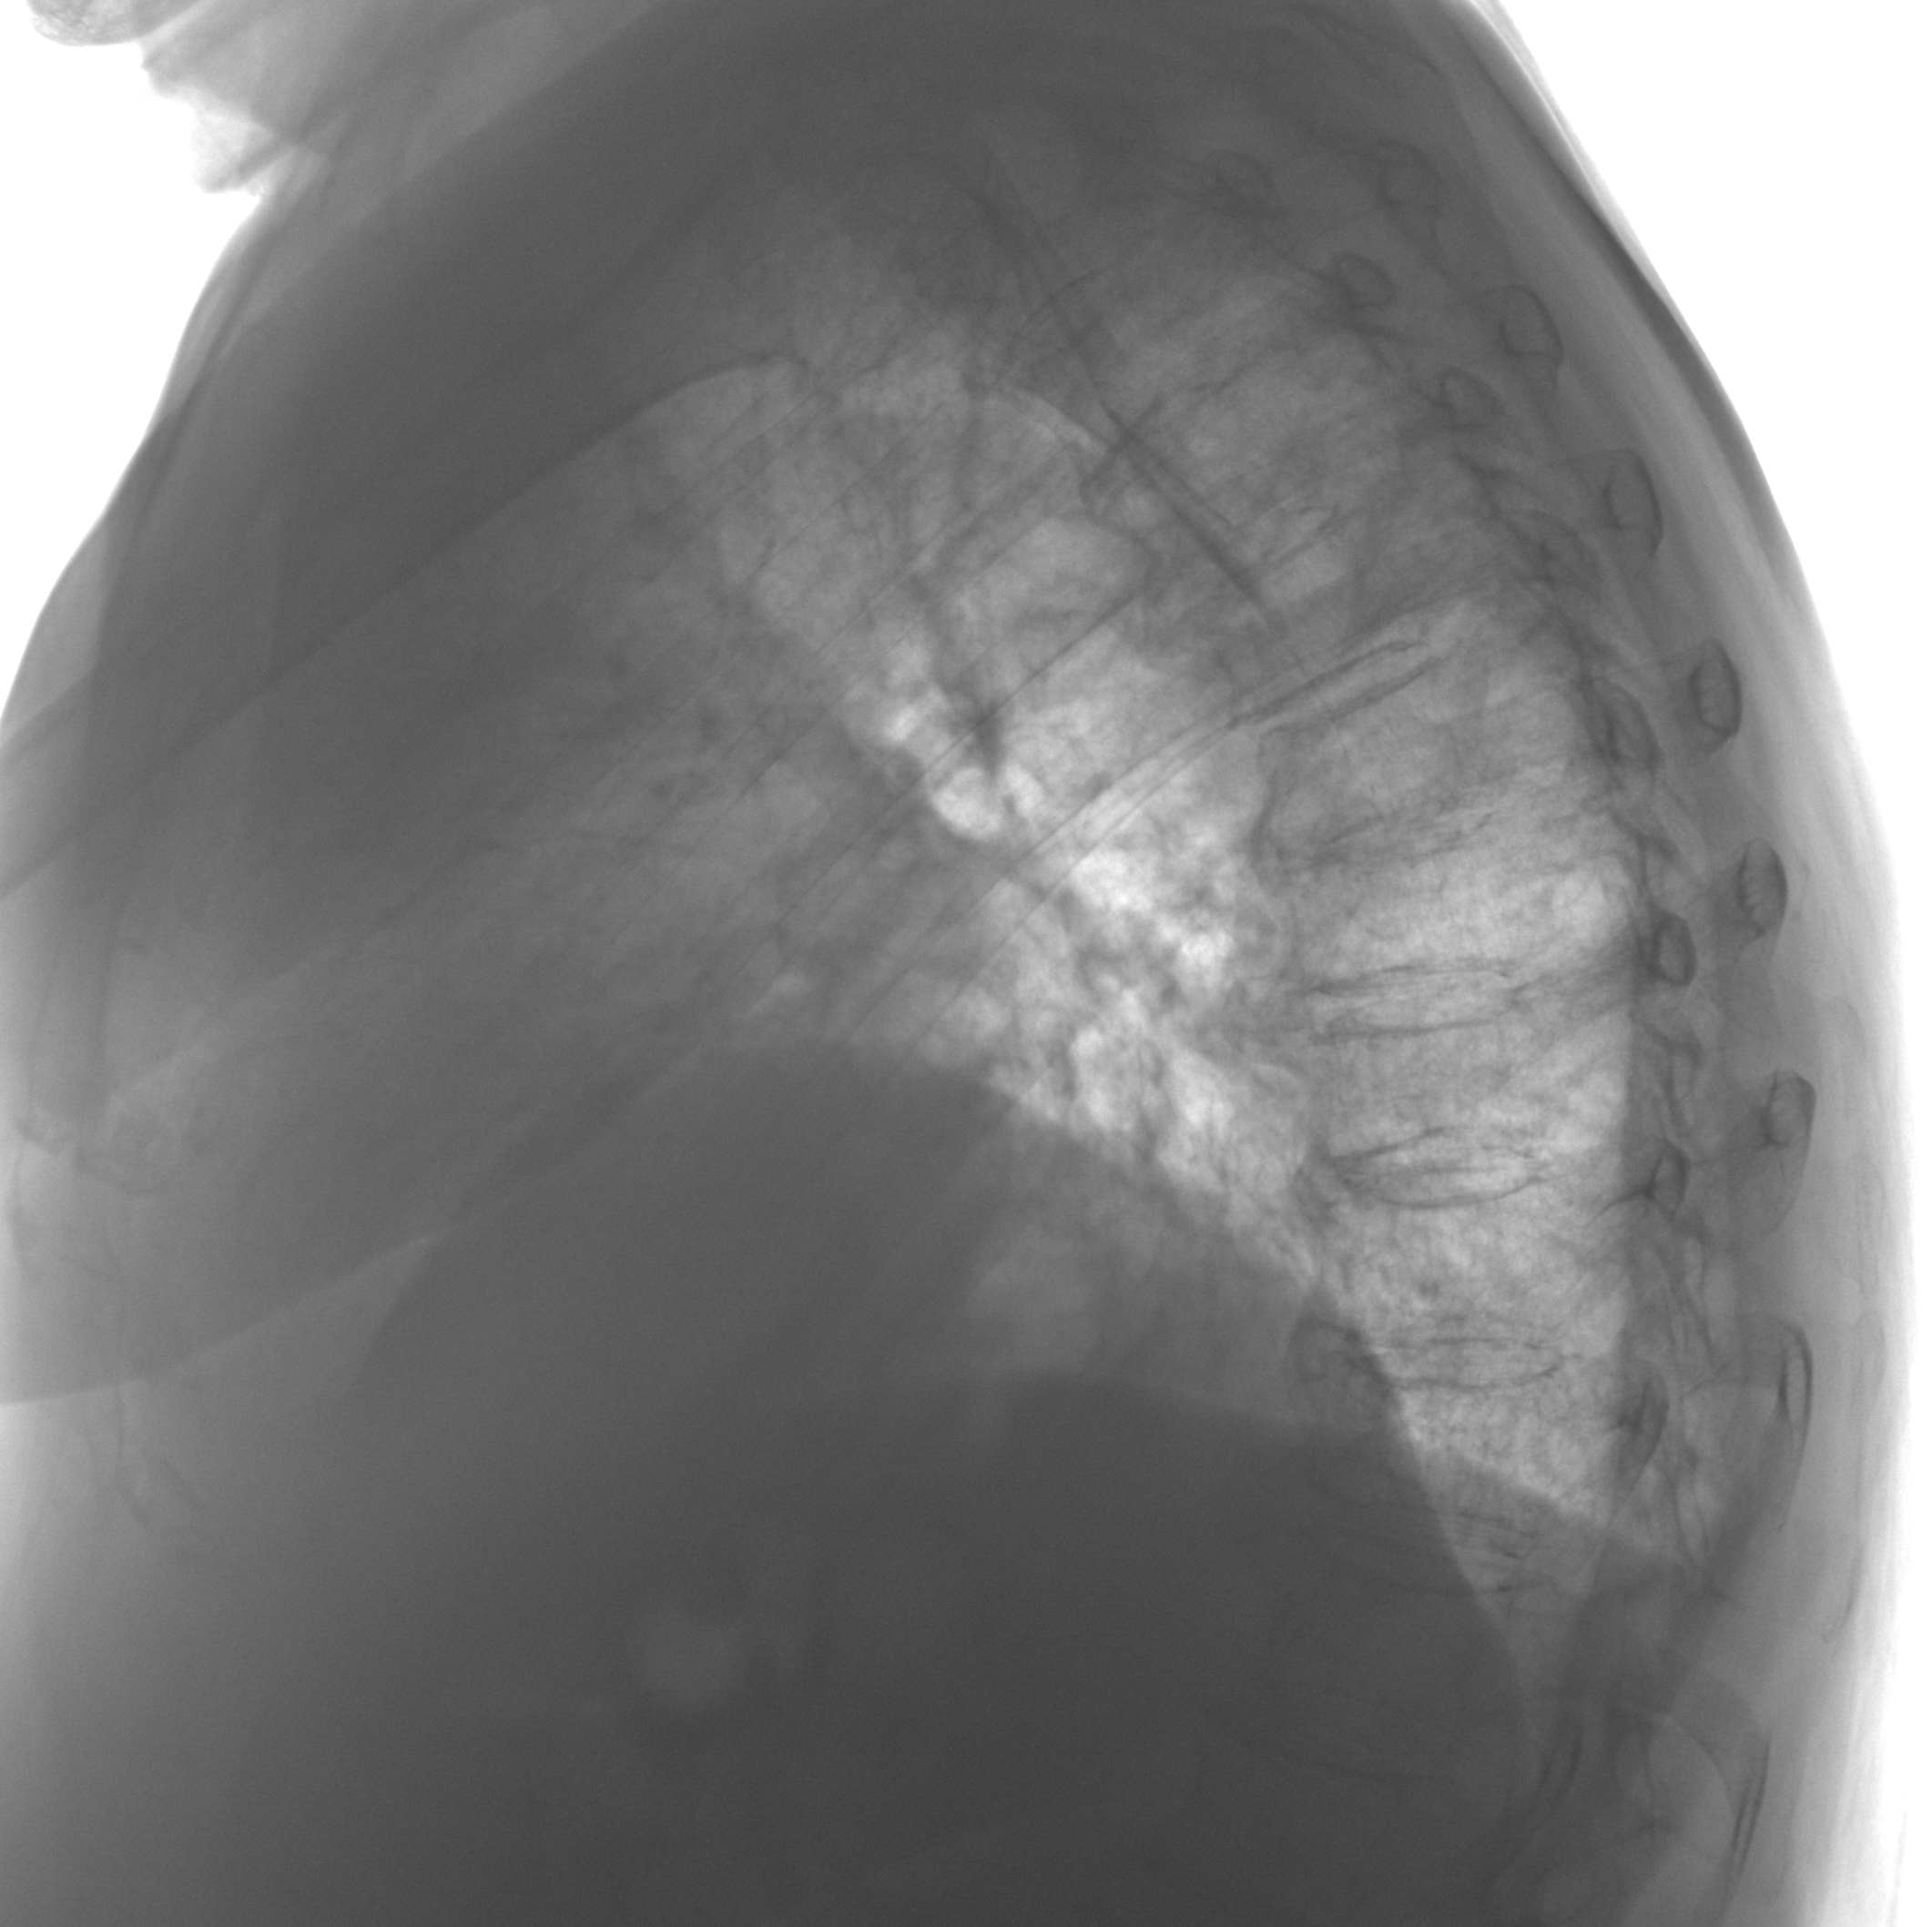

Пневмония